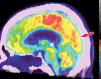

Neurodegenerative diseases are a devastating group of disorders that can be difficult to accurately diagnose. Although these disorders are difficult to manage owing to relatively limited treatment options, an early and correct diagnosis can help with managing symptoms and coping with the later stages of these disease processes. Both anatomic structural imaging and physiologic molecular imaging have evolved to a state in which these neurodegenerative processes can be identified relatively early with high accuracy. To determine the underlying disease, the radiologist should understand the different distributions and pathophysiologic processes involved. High-spatial-resolution MRI allows detection of subtle morphologic changes, as well as potential complications and alternate diagnoses, while molecular imaging allows visualization of altered function or abnormal increased or decreased concentration of disease-specific markers. These methodologies are complementary. Appropriate workup and interpretation of diagnostic studies require an integrated, multimodality, multidisciplinary approach. This article reviews the protocols and findings at MRI and nuclear medicine imaging, including with the use of flurodeoxyglucose, amyloid tracers, and dopaminergic transporter imaging (ioflupane). The pathophysiology of some of the major neurodegenerative processes and their clinical presentations are also reviewed; this information is critical to understand how these imaging modalities work, and it aids in the integration of clinical data to help synthesize a final diagnosis. Radiologists and nuclear medicine physicians aiming to include the evaluation of neurodegenerative diseases in their practice should be aware of and familiar with the multiple imaging modalities available and how using these modalities is essential in the multidisciplinary management of patients with neurodegenerative diseases.©RSNA, 2020.